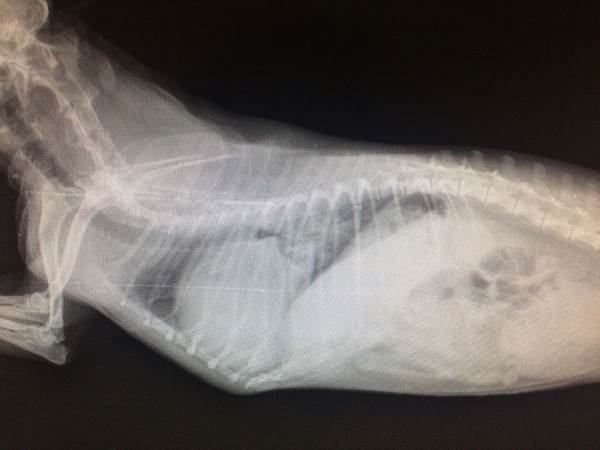

Диагностика отека легких у кошек основана на истории болезни, клинической симптоматике, аускультации (прослушивание шумов легких) и рентгенографии. Однако, если кошка находится в критическом состоянии и есть угроза жизни, первичное лечение необходимо проводить без дополнительной диагностики до стабилизации состояния.